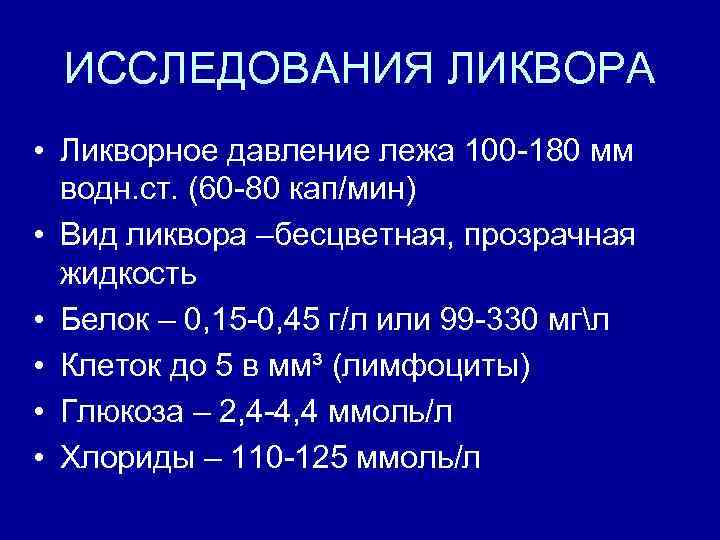

ИССЛЕДОВАНИЯ ЛИКВОРА • Ликворное давление лежа 100 -180 мм водн. ст. (60 -80 кап/мин) • Вид ликвора –бесцветная, прозрачная жидкость • Белок – 0, 15 -0, 45 г/л или 99 -330 мгл • Клеток до 5 в мм³ (лимфоциты) • Глюкоза – 2, 4 -4, 4 ммоль/л • Хлориды – 110 -125 ммоль/л

ИССЛЕДОВАНИЯ ЛИКВОРА • Ликворное давление лежа 100 -180 мм водн. ст. (60 -80 кап/мин) • Вид ликвора –бесцветная, прозрачная жидкость • Белок – 0, 15 -0, 45 г/л или 99 -330 мгл • Клеток до 5 в мм³ (лимфоциты) • Глюкоза – 2, 4 -4, 4 ммоль/л • Хлориды – 110 -125 ммоль/л